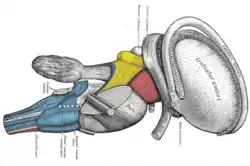

Dissection of brain-stem. Lateral view. Superficial dissection of brain-stem. Ventral view.

Superficial dissection of brain-stem. Ventral view. The motor tract.

The motor tract.